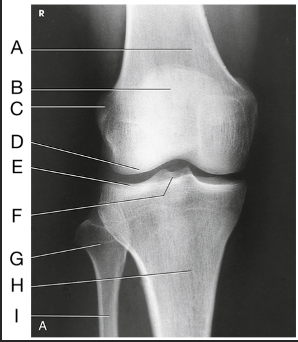

Name this projection

AP knee

Where does the CR enter for this projection?

½" inferior to patellar apex

If the patient is sthenic (19-24 cm) how is the CR directed?

0 degrees (perpendicular to IR)

Label the image: A

femur

Label the image: B

patella

Label the image: C

lateral femoral epicondyle

Label the image: D

lateral femoral condyle

Label the image: E

Lateral tibial plateau

Label the image: F

intercondylar eminence

Label the image: G

head of fibula

Label the image: H

tibia

Label the image: I

fibula